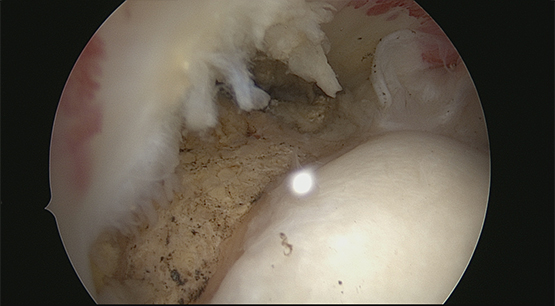

Visualisation du bec acromial et sa résection (acromioplastie).

Acromioplastie en cours

Acromioplastie